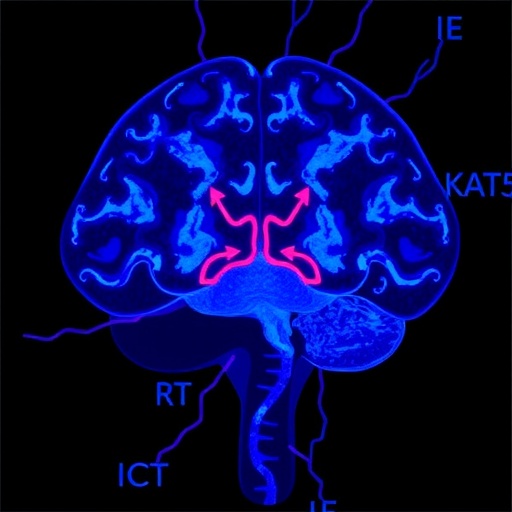

At the heart of this new study lies KAT5, a lysine acetyltransferase better known as TIP60, which historically has been studied for its roles in DNA damage repair, chromatin remodeling, and transcriptional regulation. The team led by Mihalas, Arora, O’Connor, and colleagues applied multi-dimensional single-cell transcriptomic and epigenomic profiling techniques to dissect the cellular architecture of human glioblastoma samples. Their data illuminated how KAT5 activity directs the epigenetic programming that establishes and maintains neurodevelopmental trajectories within G0-like tumor cell populations.

Crucially, the authors demonstrated that KAT5 is not merely a passive participant but an active regulator capable of toggling glioblastoma cells between proliferative and quiescent neurodevelopmental states. This finding is revolutionary because it positions KAT5 as a molecular switch that maintains the balance between tumor growth and dormancy, thereby fostering cell populations that can evade standard therapies targeting rapidly dividing cells. The presence of G0-like cells endowed with stem-like features creates a reservoir of therapy-resistant cells—essentially the seeds of tumor relapse.

Mechanistically, the study uncovered that KAT5 recruitment leads to acetylation of specific histone marks at promoters and enhancers of developmental genes, resulting in the activation of neural progenitor and stem-like transcriptional programs. This epigenetic modulation confers plasticity upon glioblastoma cells, enabling them to adapt dynamically to microenvironmental stresses, including hypoxia, nutrient deprivation, and therapeutic insults. The intricate crosstalk between chromatin remodeling and neurodevelopmental signaling orchestrated by KAT5 underscores the complexity of glioma biology.

In addition to delineating the functional impact of KAT5 on glioblastoma cellular hierarchies, the scientists identified downstream transcription factors and signaling pathways—such as SOX2 and Notch—that synergize with KAT5’s activity to stabilize the quiescent neurodevelopmental phenotype. These interactions create a self-reinforcing network that preserves tumor cell dormancy and adaptability, offering multiple molecular nodes for pharmacological disruption.